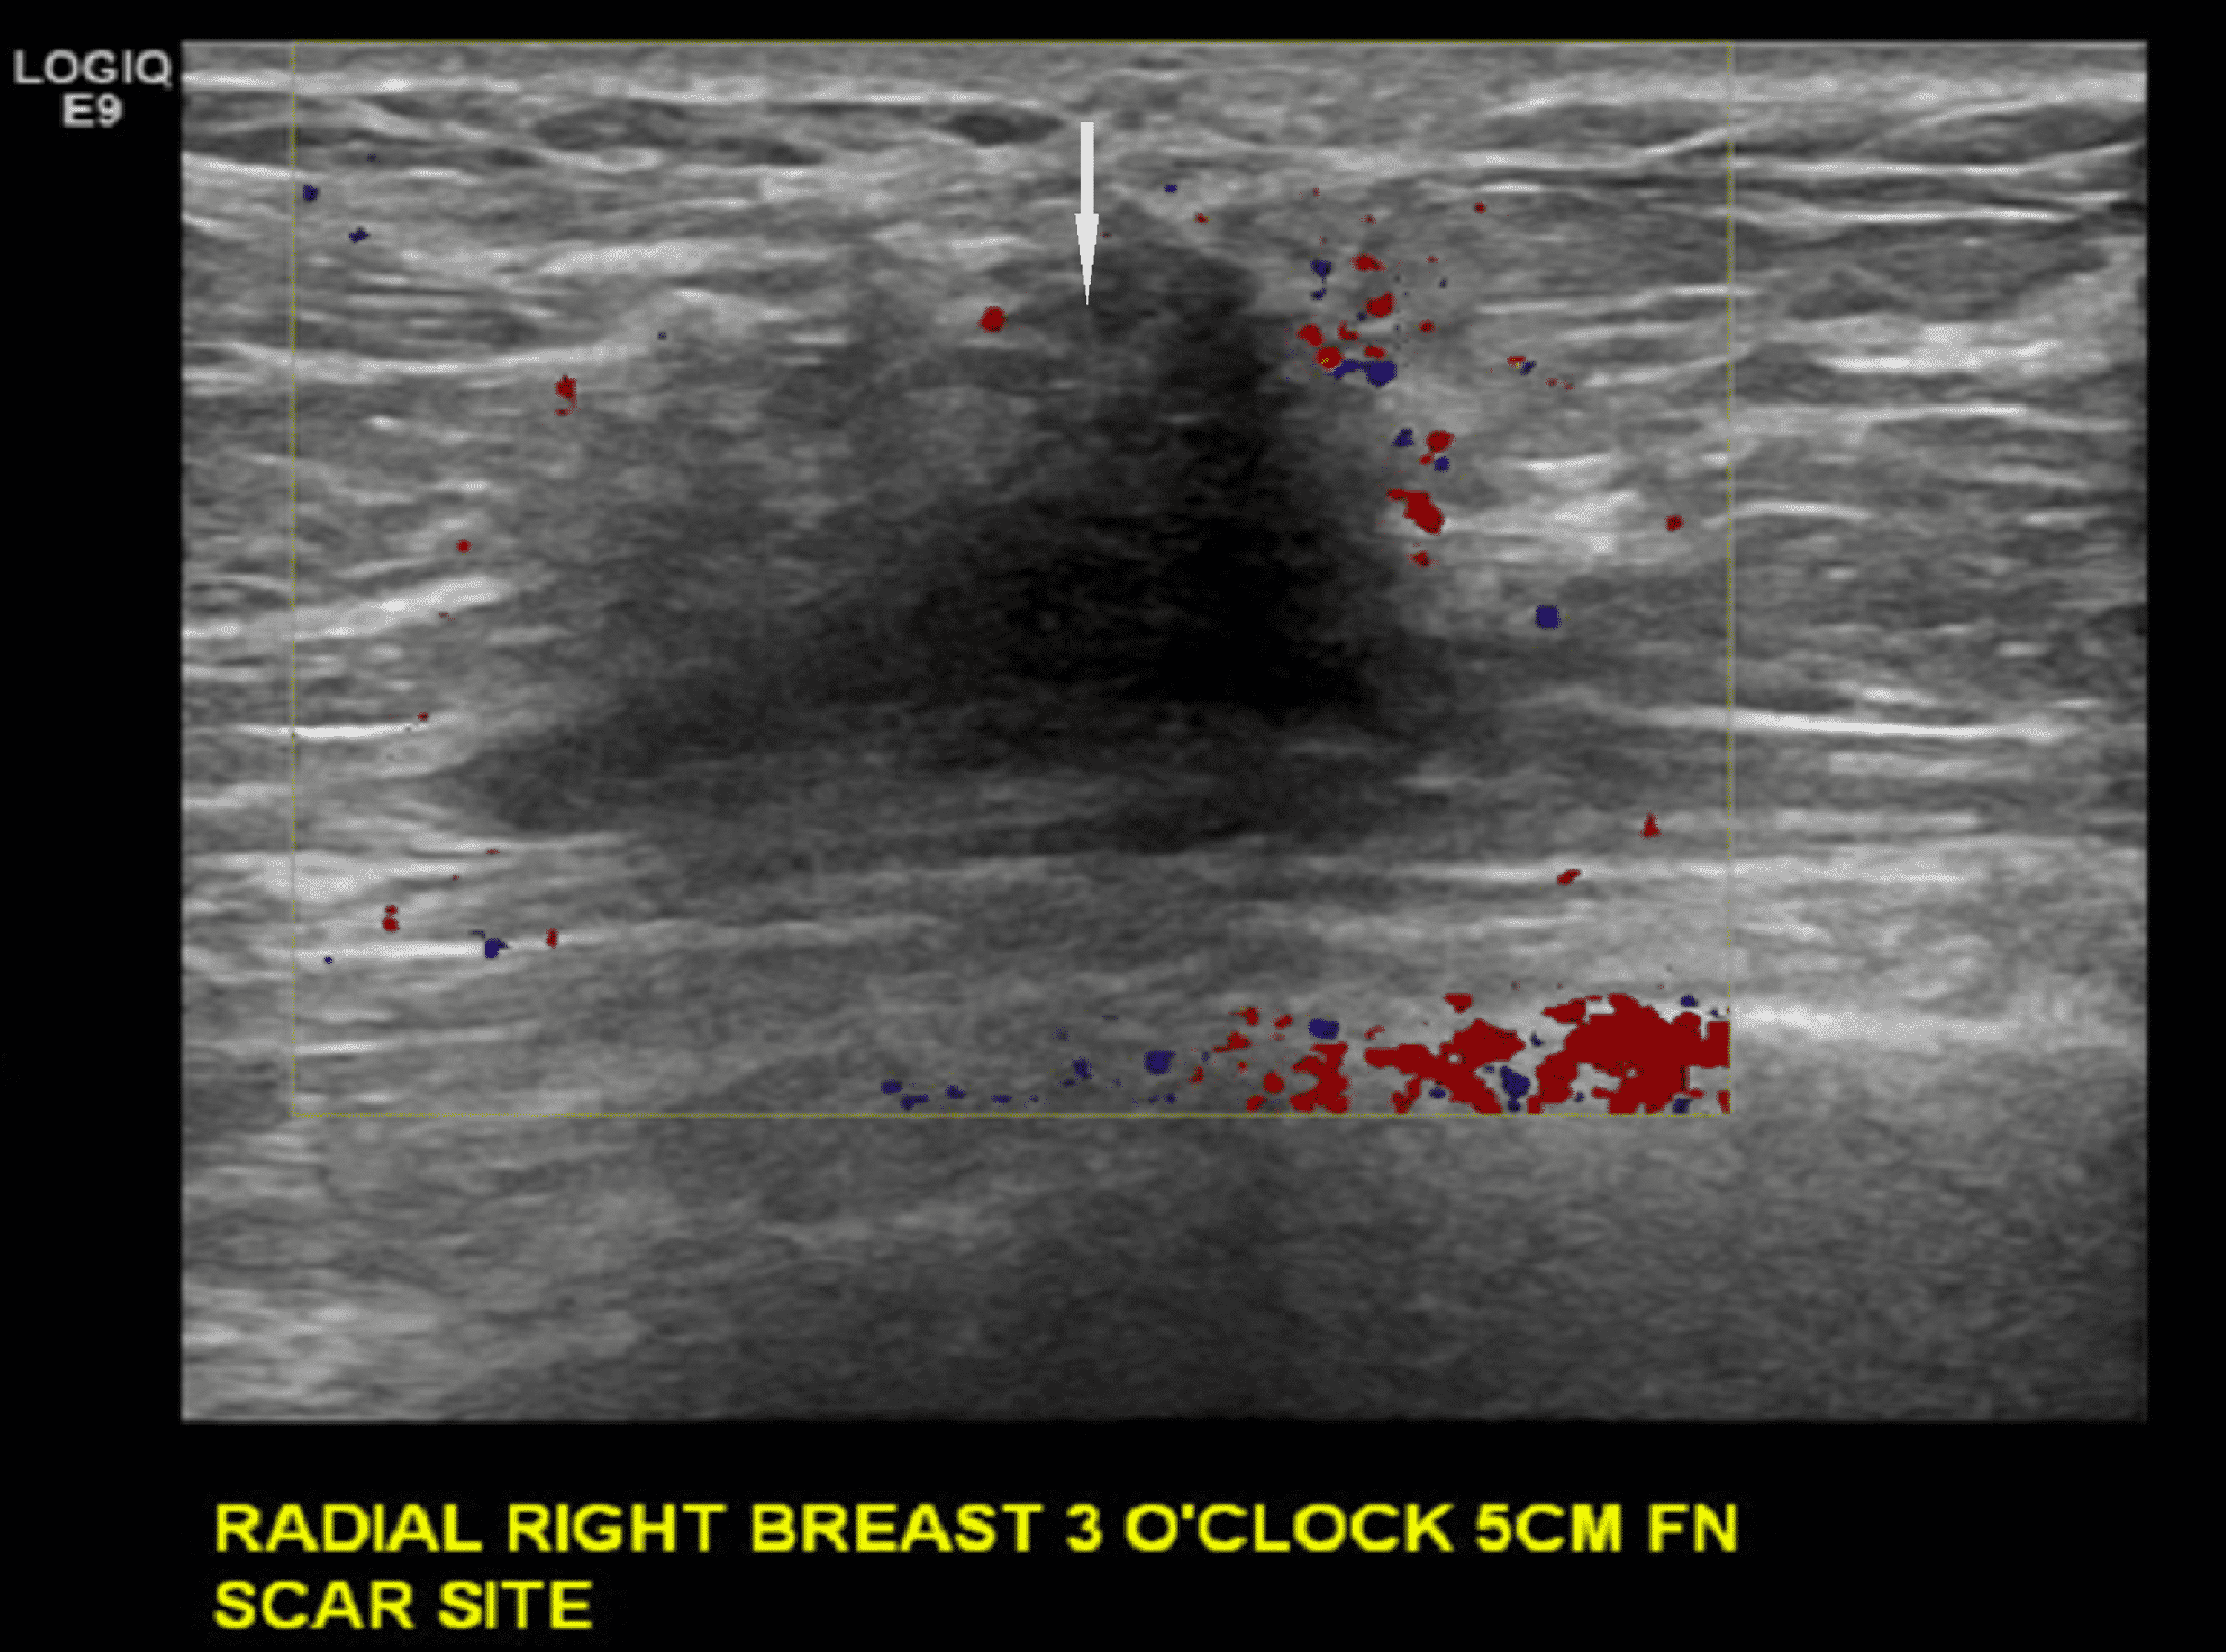

Cureus Invasive Lobular Cancer Arising in a Surgical Scar From Best Cream For Lumpectomy Scar Any moisturiser can be used, as long as it does not contain too much perfume; Following a lumpectomy, tingling and mild pain around the scar are common complaints during the first few days. Your surgeon may have put. Two weeks from now, when your skin is a little less bruised, when your incision is healing even further, now you can. Best Cream For Lumpectomy Scar.